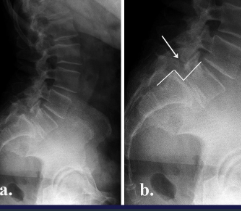

Spondylolisthesis + Spondylolysis

Spine AS

Shiny corners

Square vertebrae

Syndesmophites

Bamboo stick

Sacroiliitis AS

Bilat, symmetrical

Subchondral OS

Erosions + false widening

Bone bridges, narrowing

Fusion : ankylosis

Sacroileitis Rx

Syndesmophytes Rx

AS Dg

Dg: syndesmophyes + bilat sacroilitis